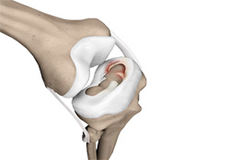

Articular Cartilage and Menisci of the Knee

Movement of the bones causes friction between the articulating surfaces. To reduce this friction, all articulating surfaces involved in the movement are covered with a white, shiny, slippery layer called articular cartilage. The articulating surface of the femoral condyles, tibial plateaus and the back of the patella are covered with this cartilage. The cartilage provides a smooth surface that facilitates easy movement.

Within the knee joint, between the femur and tibia, are two C-shaped cartilaginous structures called menisci. Menisci function to provide stability to the knee by spreading the weight of the upper body across the whole surface of the tibial plateau. The menisci help in load-bearing i.e. it prevents the weight from concentrating onto a small area, which could damage the articular cartilage. The menisci also act as a cushion between the femur and tibia by absorbing the shock produced by activities such as walking, running and jumping.